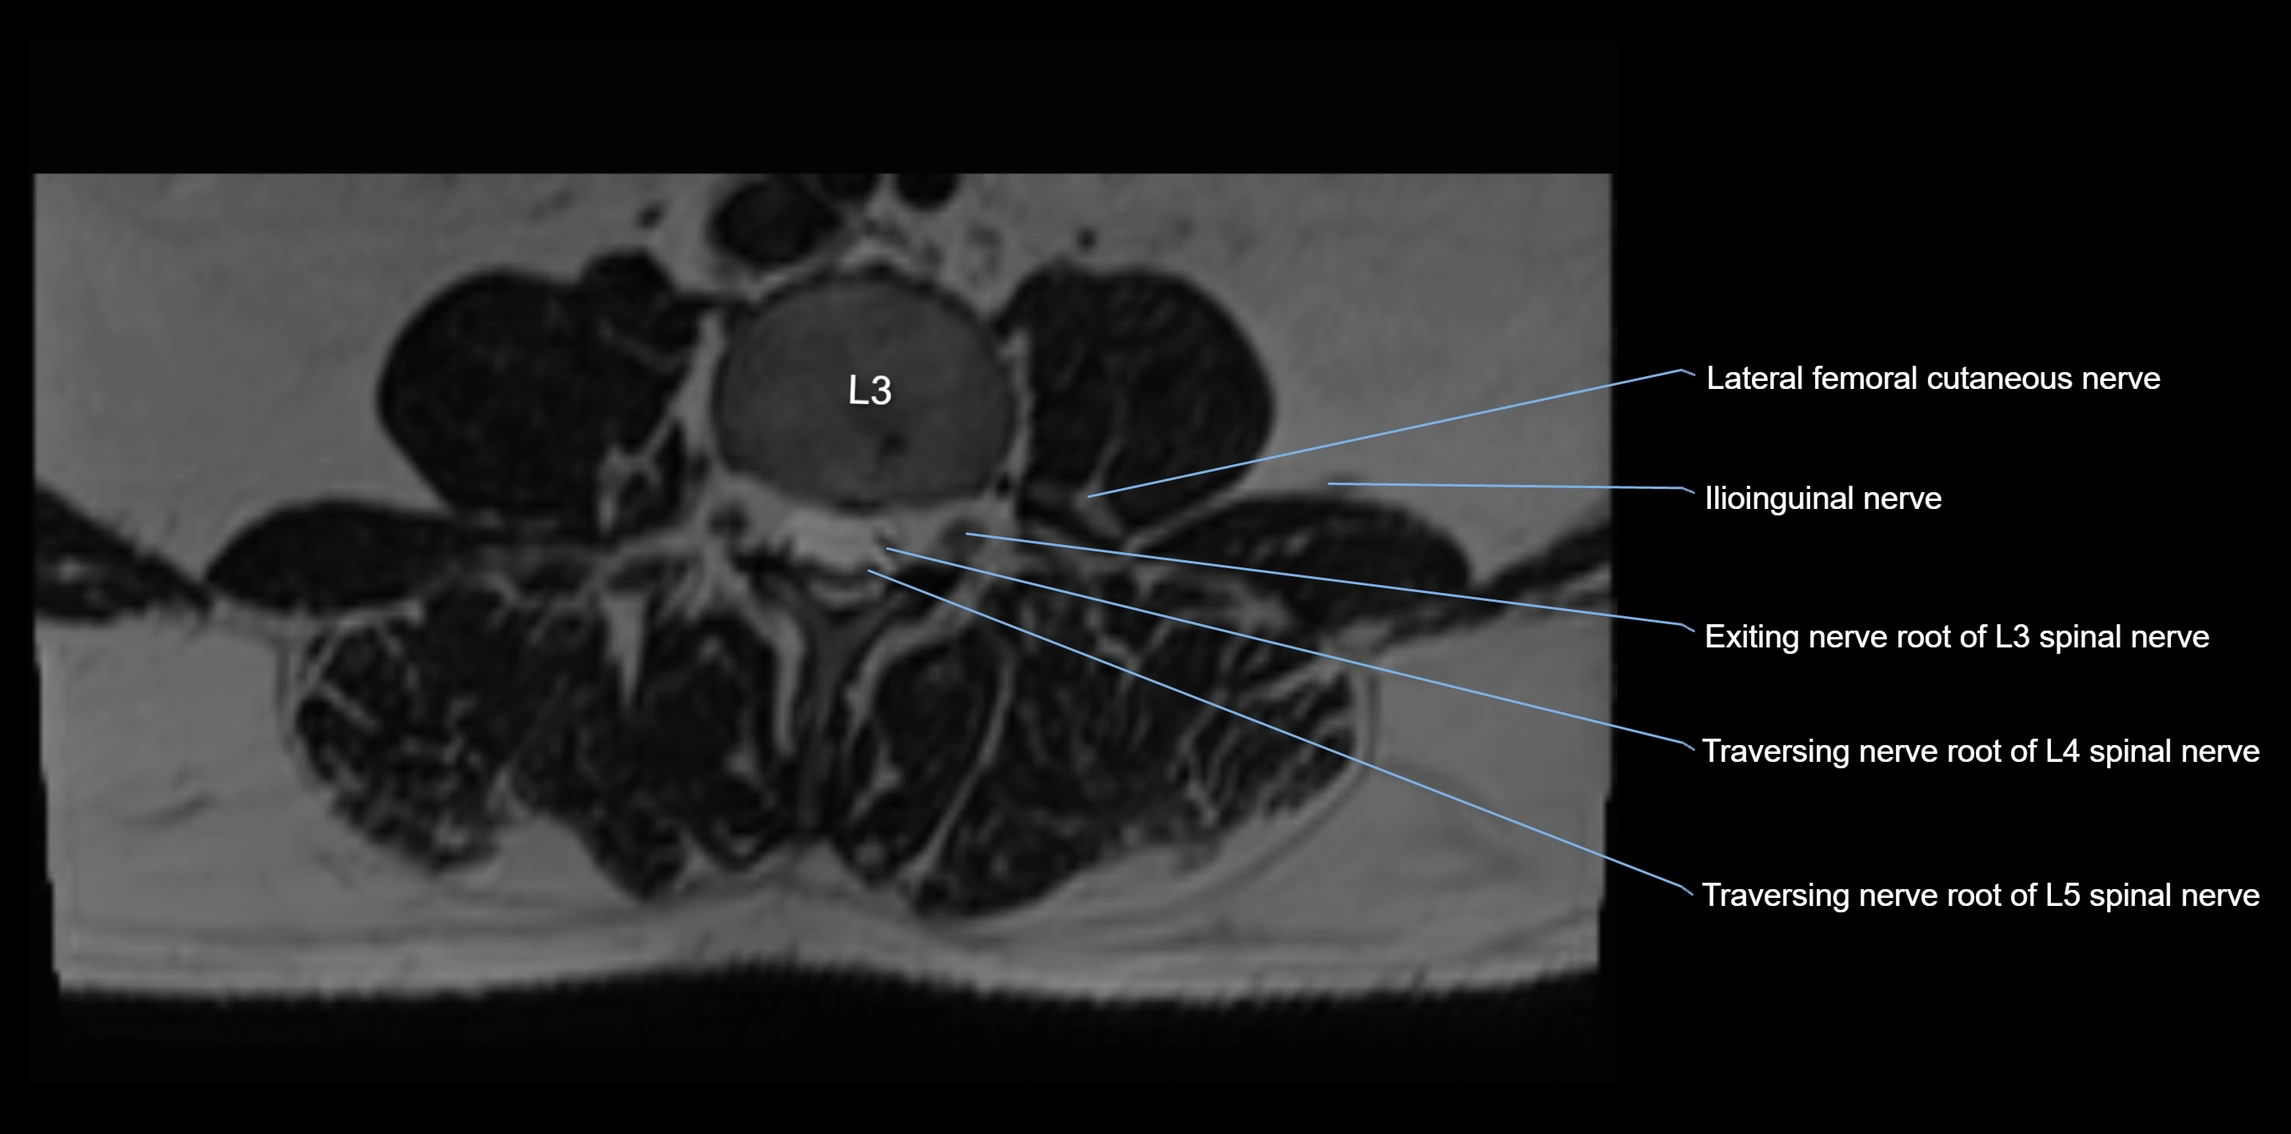

MRI image

image